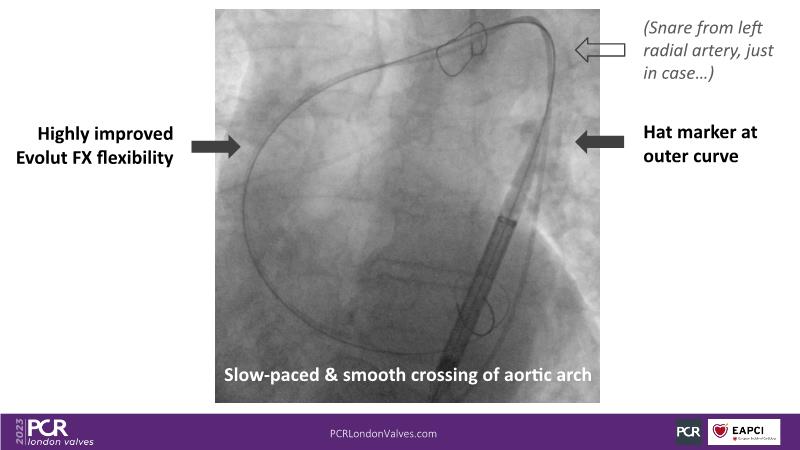

Defying complexity: achieving optimal TAVI procedural outcomes in challenging anatomies with the new Evolut FX

Watch this session to understand factors to consider when deciding on valve selection, recognize the significance of device choice and implantation technique in redo-TAVI, and acquire insights into anticipating challenges associated with implanting a bicuspid valve, large anatomy, and a horizontal aorta.

- To learn how to anticipate the challenges of implanting a bicuspid valve, large anatomy, horizontal aorta